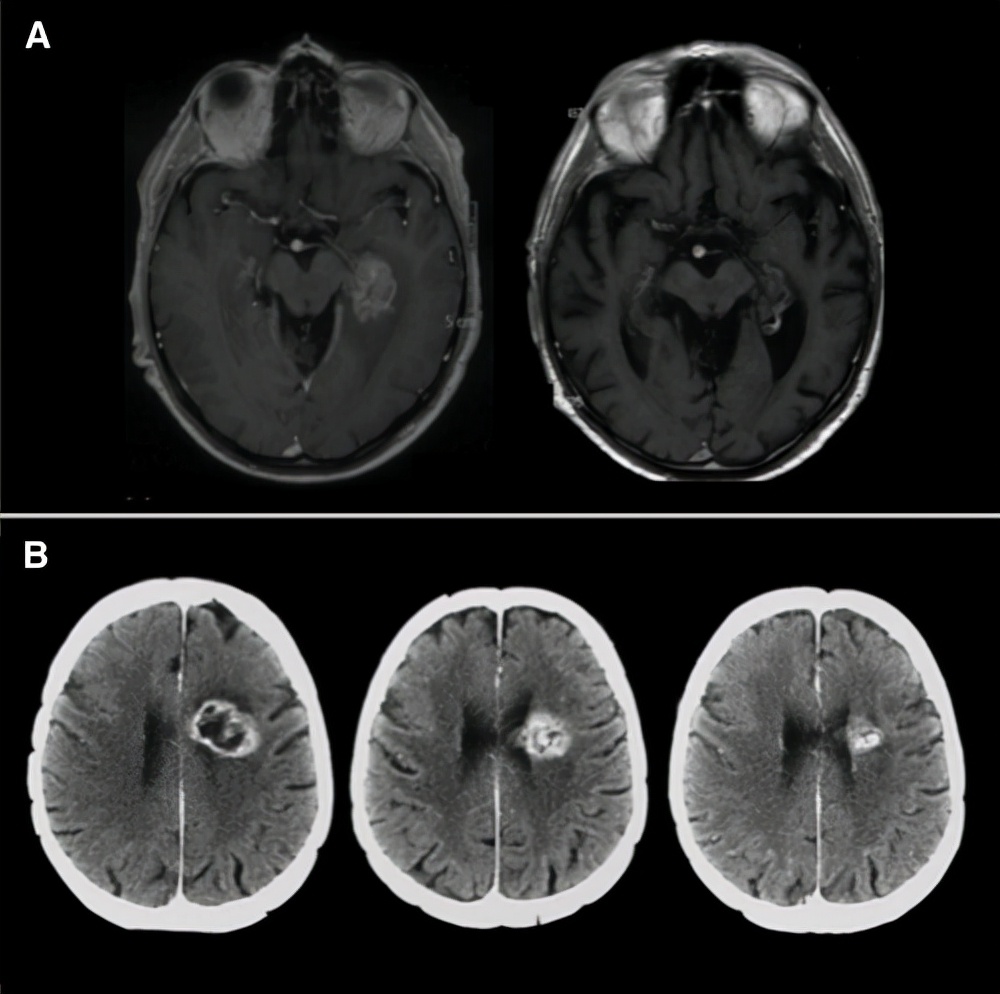

图示:3级胶质瘤老年患者的积极案例。(A):左:70岁患者术前磁共振成像(MRI)。病人接受了病变的活检。明确诊断为无1p/19q共缺失,IDH1突变3级少突胶质细胞瘤。患者进一步接受放射治疗,同时辅以替莫唑胺。右图:诊断后7年进行的脑核磁共振成像,显示持续完全缓解。卡诺夫斯基的表现得分是80%。(B):左:74岁患者活检后脑CT扫描图。病理诊断为3级少突胶质细胞瘤。中:前期替莫唑胺治疗4个周期后CT扫描,显示部分缓解。右图:预先用替莫唑胺治疗12个周期后的CT扫描,显示部分反应。无进展生存期为25个月。